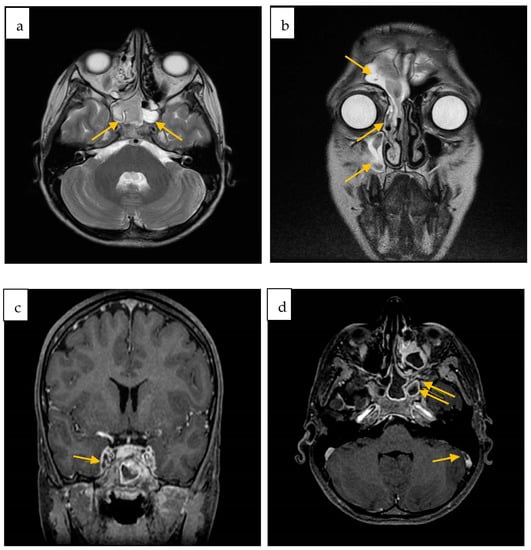

2. Case Report